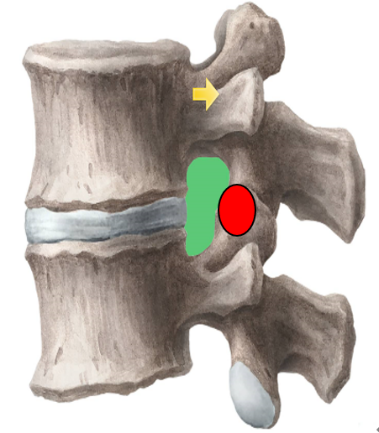

为解决以上问题,我们提出“椎间孔镜按需成型5级法”,即将椎间孔镜术中椎间孔成型的实际操作范围进行分级:0级:不成型,见图 1;1级:软组织成型,只去除关节囊等部分软组织,基本不做骨性成型,见图 2;2级:少许骨质成型,但不显露下关节突关节面,见图 3。3级成型:上关节突尖部或上1/2去除成型,显露下关节突关节面,见图 4;4级成型:上关节突大部分成型或伴有部分椎弓、峡部或下关节突小部分,但预留基底部一部分,见图 5。